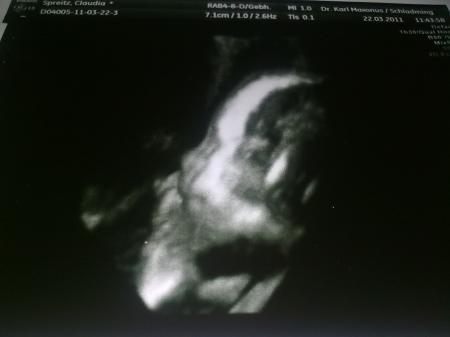

und noch ein supersüßes Foto!!! Ich bin total verliebt...

Bild zu